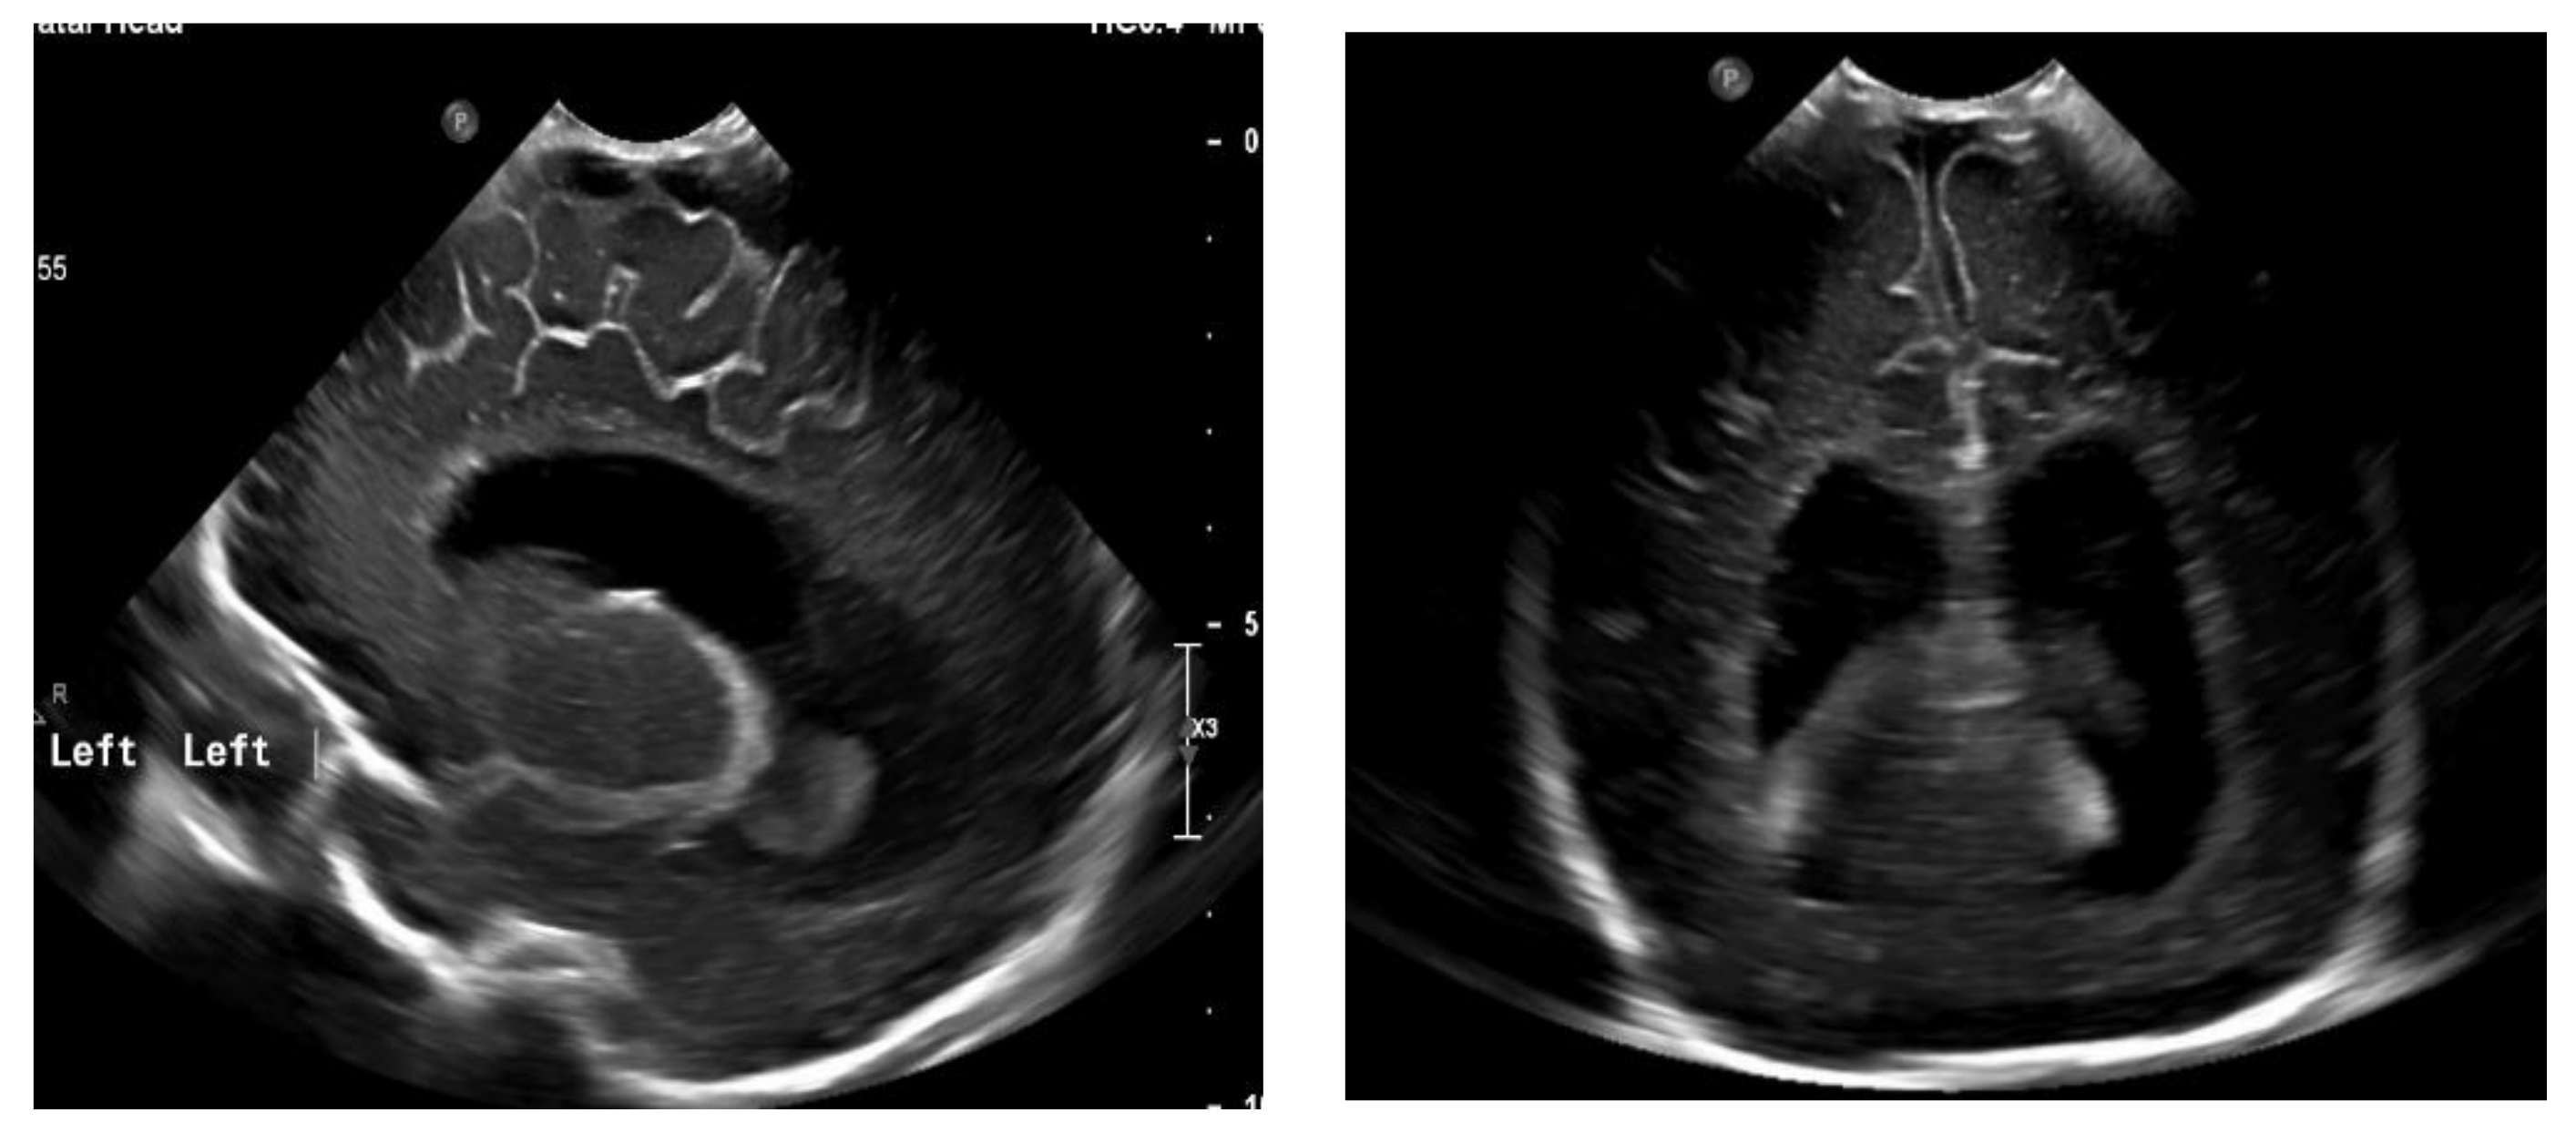

The next follow-up test, a fontanelle ultrasound, was performed every 5–7 days of neonatal life to assess the size of the cerebral ventricles and location of the posterior fossa structures. The dynamics of hydrocephalus progression was assessed based on the measurements of the lateral ventricular size (anterior horns and stem) and increased resistance index of the anterior cerebral artery (RI ACA) on follow-up ultrasound, as well as the measurements of the head circumference and palpable tension of the anterior fontanelle. The measurements were then used to determine the need to place Ventriculo-Peritoneal shunt (V-P-shunt) if the anterior horn and lateral ventricular size exceeded the 90th percentile on the pediatric ultrasound scale, and continued rising, RI ACA was >0.75, and increased tension of the anterior fontanelle failed to resolve [7,8] (Figure 3 and Figure 4).

Figure 4. Ventriculomegaly, which requires V-P shunting on fontanelle ultrasound.